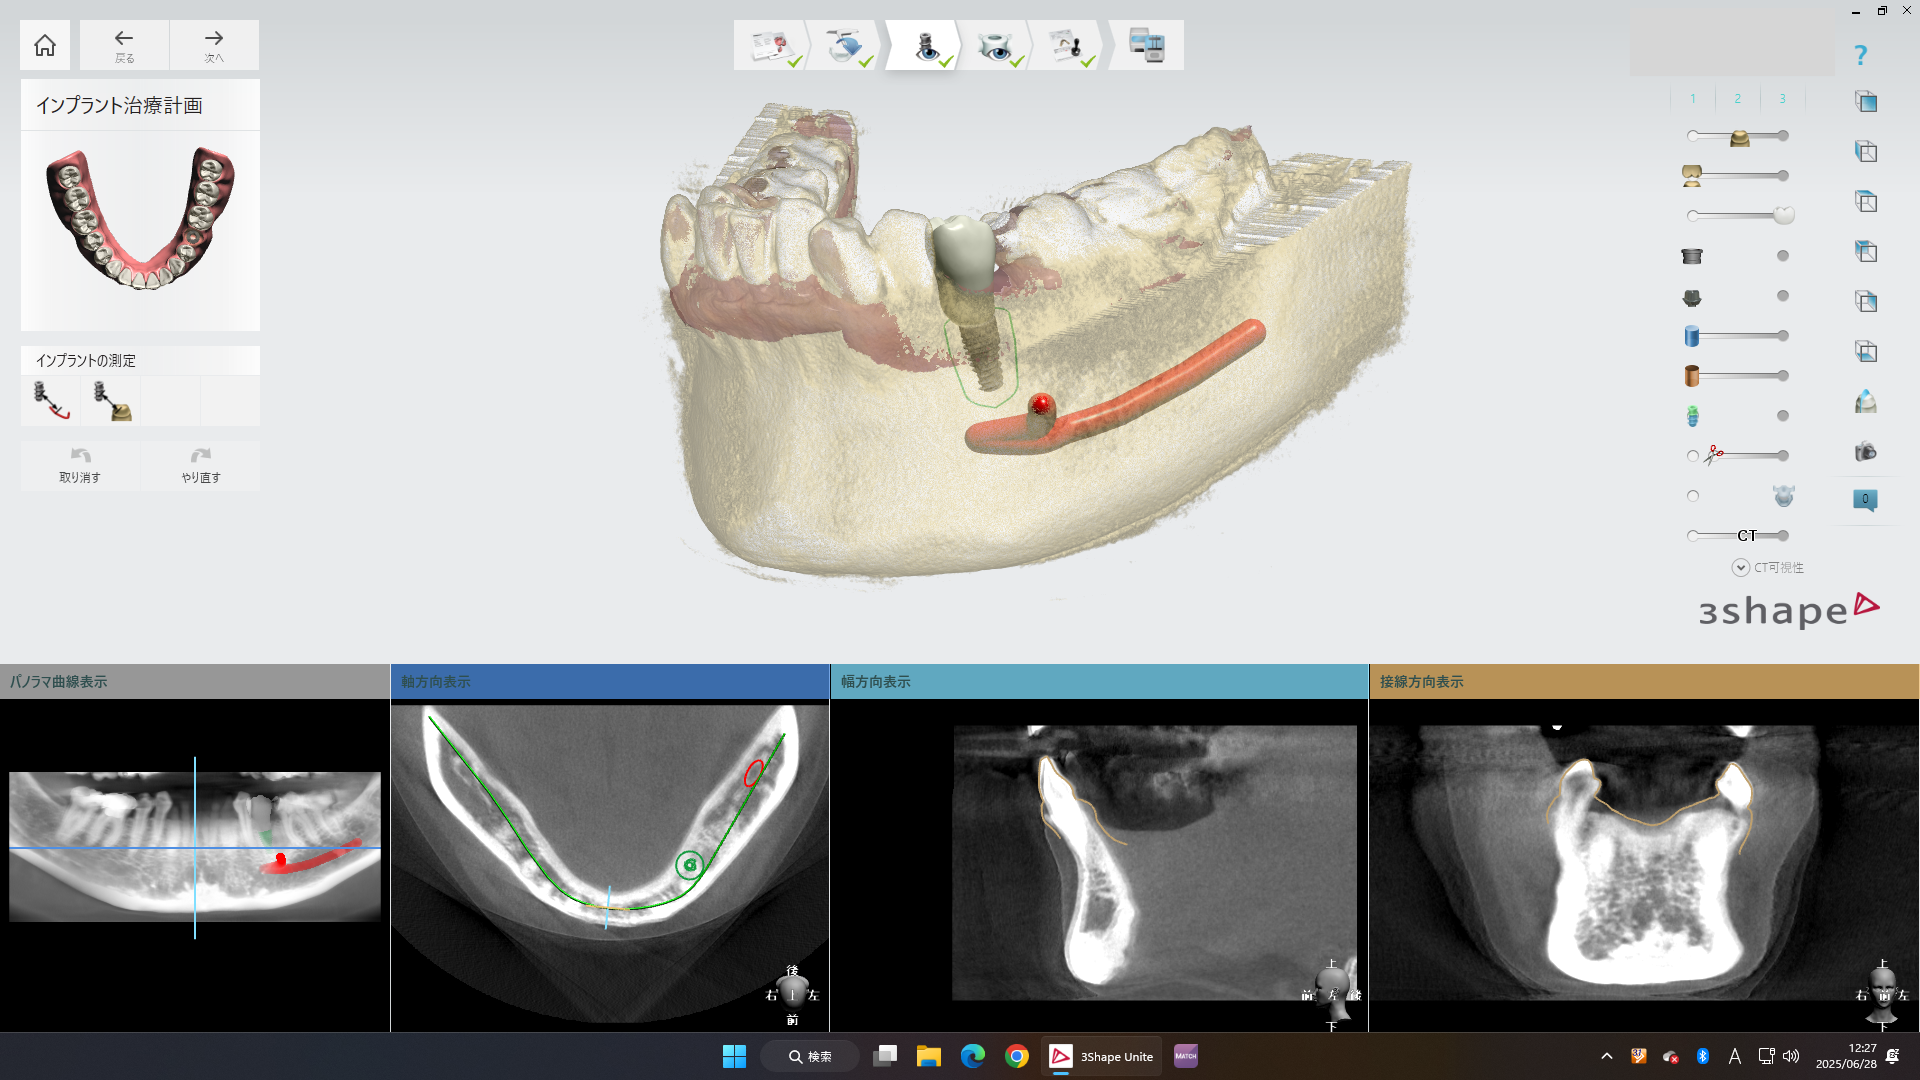

診断結果などを参考に、CTや3Dスキャンデータをインプラントシミュレーションソフトに取り込み、理想的な歯の位置に最適となるようにインプラントの埋入位置を検討して決定します。

この際に骨量が足りない場合や神経などの位置関係で理想的な位置にインプラントが埋入できないような場合には、骨造成や傾斜埋入などの代替案なども併せてご説明します。